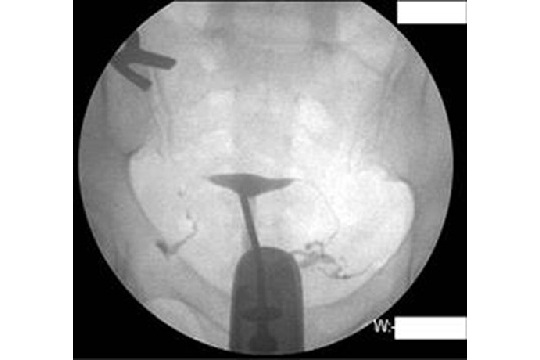

相信不少準備孕育下一代的夫妻都曾聽說過:一對夫婦若有正常性生活超過1年而未能自然成孕,已可界定為不育。但大家可知道不育的常見成因有哪一些?原來有3成不孕個案是由女方輸卵管阻塞造成;有2成是排卵障礙,如月經不正常、排卵不順甚或不排卵;另外3成則是男方精子稀少、活動力不佳等問題。就輸卵管阻塞問題,曾有女生從網上聽說輸卵管攝影會很痛,於是逃避就診,殊不知一些不孕婦女只需經由輸卵管攝影檢查,就能疏通輕微阻塞,解決多年不孕的困擾,成功得子。因此不孕夫妻應及早勇敢就醫。